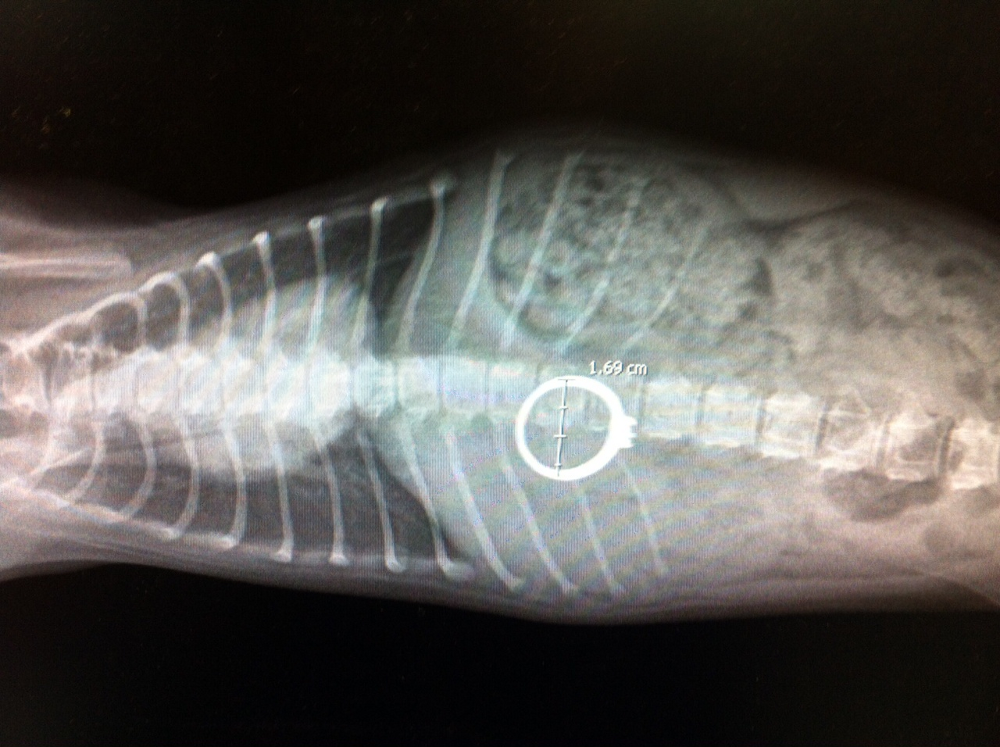

תמונות מהמרפאה